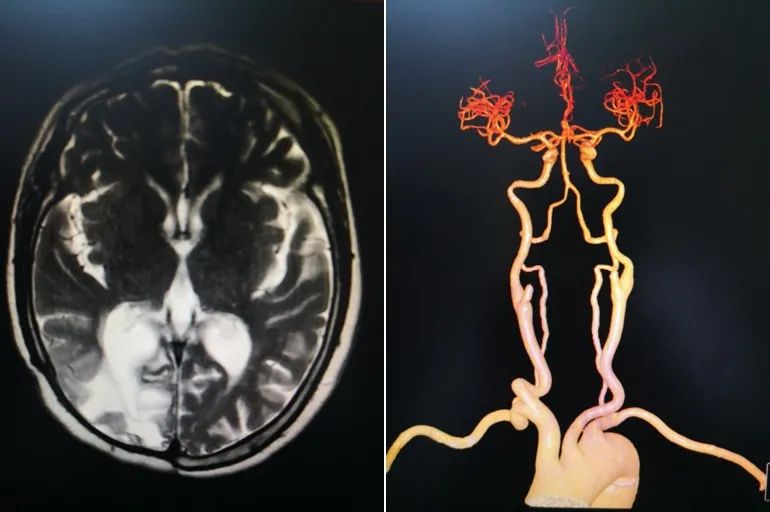

病例1情况:

患者女,58岁,四年前患脑梗死,遗留左侧肢体活动不灵,左上肢上抬不能,行走时向左侧偏斜。患者患病后长期服用 “阿司匹林肠溶片”,“瑞舒伐他汀”治疗。本次入院后经过影像学检查提示患者脑梗死软化灶近皮层,系流域性梗死,CTA提示头颈部大血管及主动脉弓无明显狭窄闭塞及不稳定斑块,临床高度怀疑心源性卒中,常规心脏彩超未见结构性心脏异常,多次常规心电图及动态心电图检测未见异常,未能明确病因诊断。

左图:头颅MRI提示右侧顶枕叶梗死灶,右图:头颈部CTA未见明显狭窄闭塞

心电图未见明显异常